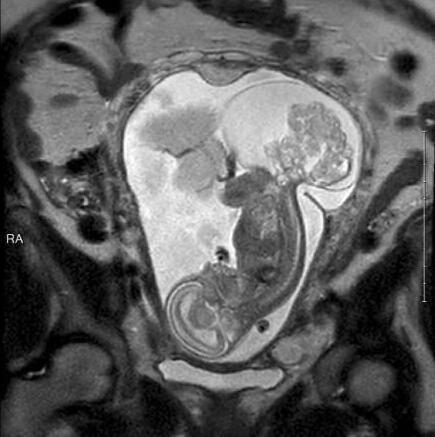

今年6月,琳莉23周零5天的時(shí)候,瑪格麗特在德克薩斯兒童醫(yī)院接受了手術(shù),這個(gè)時(shí)候的腫瘤都快比琳莉大了。手術(shù)共進(jìn)行了5個(gè)小時(shí)。“摘除腫瘤時(shí)我們做得很快,只花了20分鐘。最花時(shí)間的是打開(kāi)子宮。我們不想讓媽媽的健康受到影響,所以進(jìn)行得很仔細(xì)。”

由于腫瘤已經(jīng)很大,要取出來(lái)的話還是需要切口,所以摘除腫瘤時(shí)胎兒完全離開(kāi)了瑪格麗特的子宮,暴露在空氣中。“所有的羊水也出來(lái)了,非常神奇。”卡斯醫(yī)生說(shuō)。手術(shù)中,琳莉的心臟僅保持低頻跳動(dòng),都快停止了??ㄋ寡?qǐng)了心臟專(zhuān)家協(xié)助手術(shù)。心臟專(zhuān)家保持琳莉的心臟處于可接受的狀態(tài),以保證手術(shù)的順利進(jìn)行。